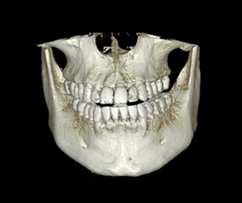

치과진료는 잇몸뼈 속 수많은 혈관과 신경, 주변 치아까지 고려한 철저한 수술계획과 노하우로 안전하게 진행해야 합니다.

간단한 식립부터 고난이도 수술까지 다양한 케이스의 수술 경험을 보유한 보건복지부 인증! 구강외과 전문의가 진료합니다.

3D CT 촬영으로 치아와 치조골의 상태 및

잇몸뼈의 양과 길이 등의 상태를 정확하게

측정하여 세밀한 진단과 시술 전 발생가능한

문제점을 사전에 발견하고 대비하여

진료의 안정성을 높힙니다.

치과진료는 굉장히 세밀한 치료이기 때문에 정밀한 3D 디지털 기술을 접목하면

의료진의 판단에만 의존하던 치료를 더욱 정확하게 예측하고 진하여 오차를 줄일 수 있습니다.